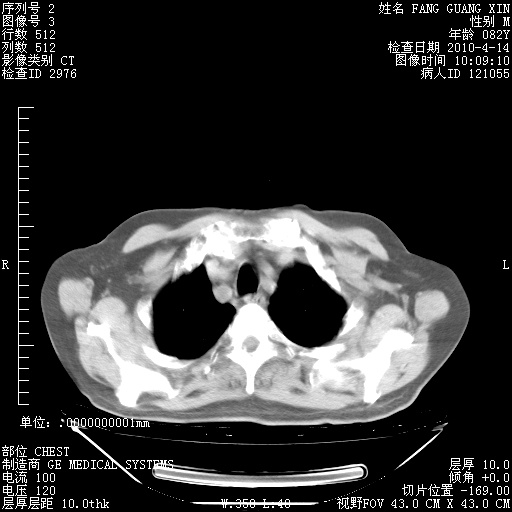

4月14日肺部CT